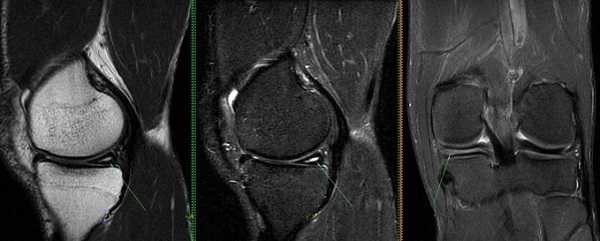

Разрыв заднего рога медиального хряща на снимках, выполненных в разных режимах, стрелка указывает на нарушение целостности пластины